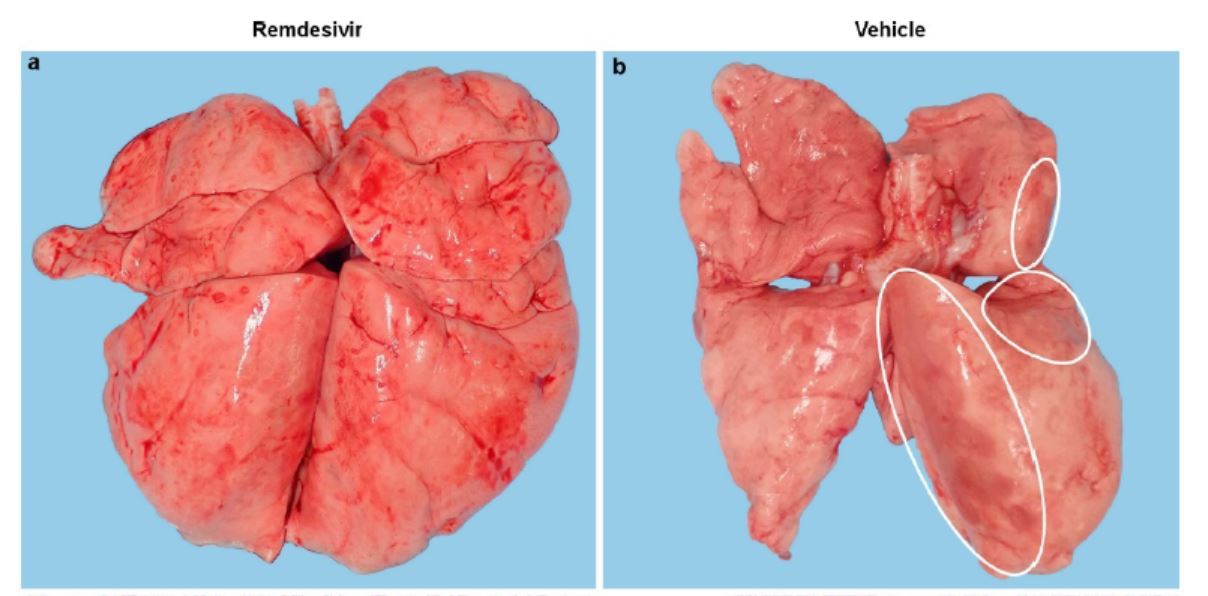

两组恒河猴代表性肺部图像对比,对照组(b)可见集中而广泛的肺部实变